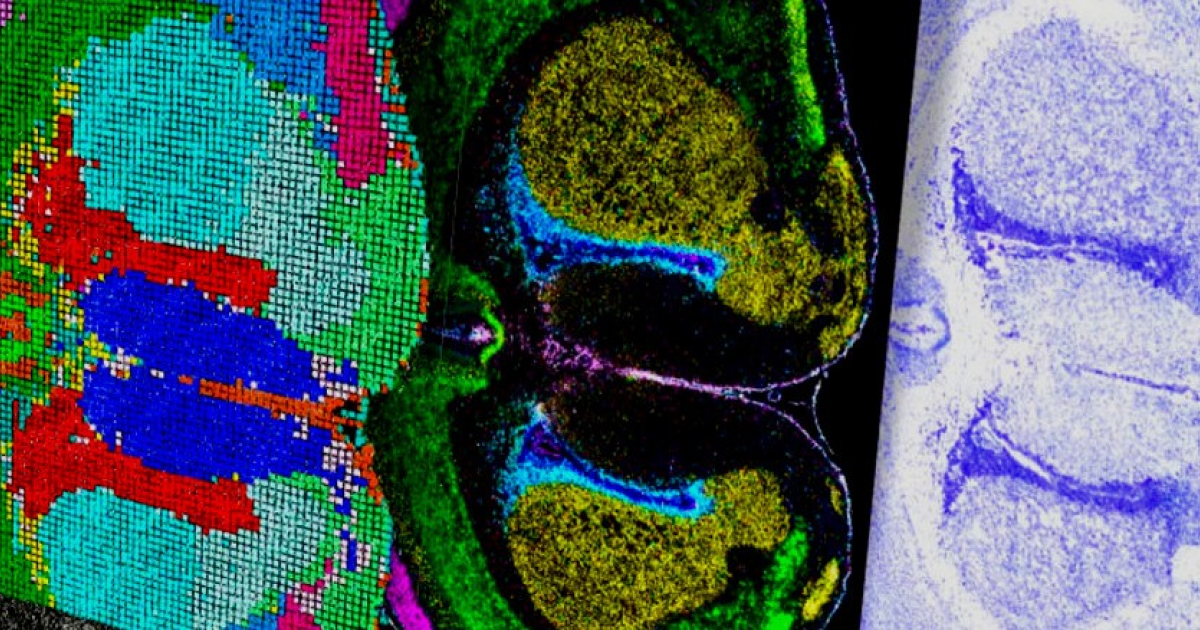

Представлены первые результаты работы над клеточным атласом развития мозга

Коллаборация американских исследователей BICAN при участии специалистов из других стран представила первые результаты работы над клеточным атласом развития мозга мыши, макаки и человека от эмбрионального периода до взрослого возраста. Посвященные этому 12 научных статей, их обобщенный обзор и редакционные материалы собраны в коллекцию журнала Nature.